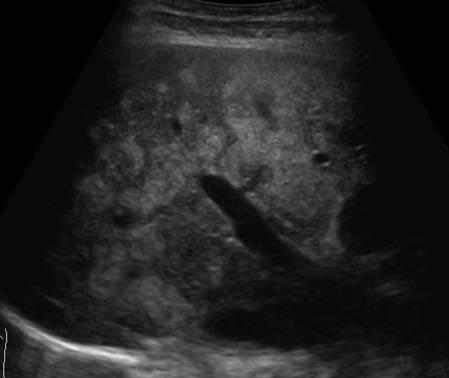

Gan nhiễm mỡ

Gan nhiễm mỡ - Ảnh 3

» Thông tin: Nữ giới – 40 tuổi.

» Lâm sàng: Kiểm tra sức khỏe.